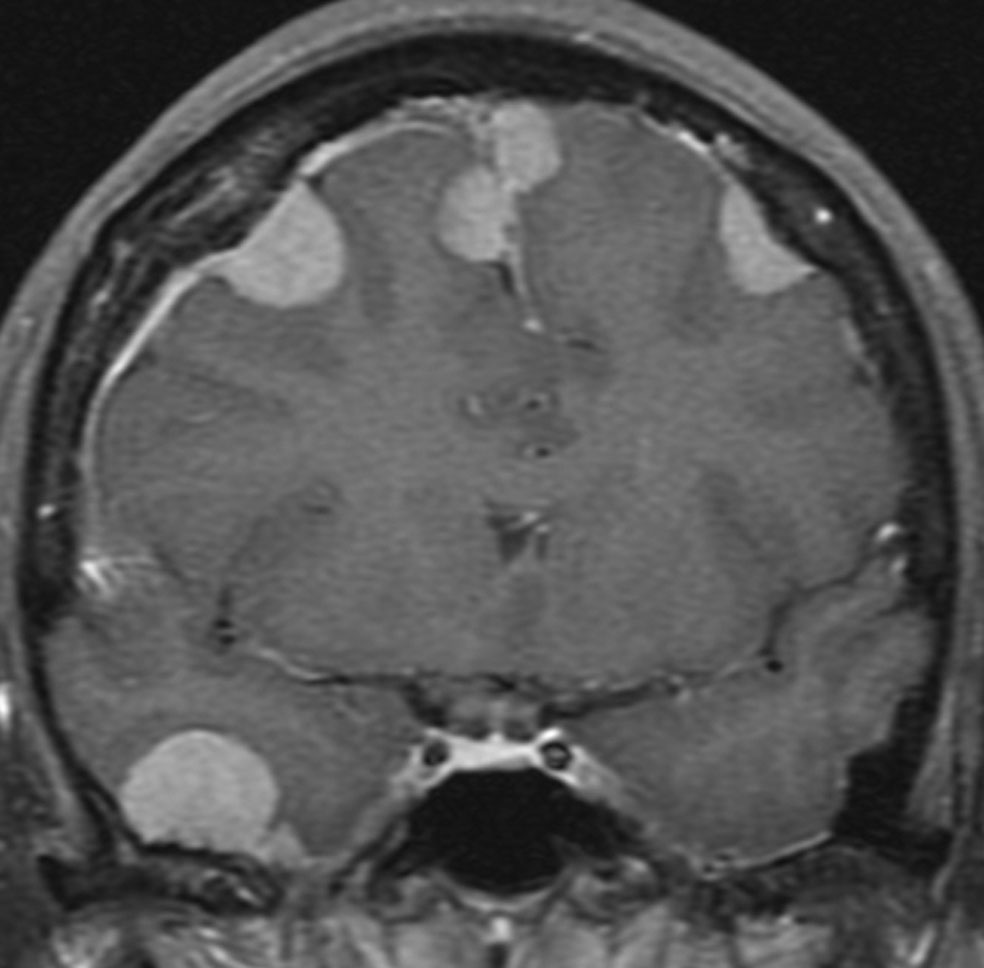

多発例,NF-2ではないもの

30代で下肢の局所てんかん発作で発見されました。テント上硬膜の腫瘍化です。数えれば総数で30個以上はあったでしょう。このタイプは手術で硬膜を広範囲切除(ほとんど全頭蓋冠)することで治すことができます。